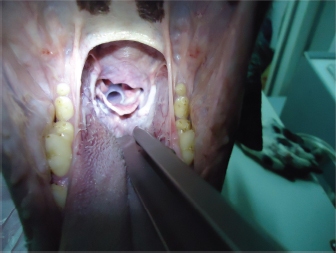

Once the stent is placed, titrated propofol IV is suspended and an oxygen face mask is again used until the dog recovers. It is necessary to check if the stent is correctly placed during this time. It might provoke a discrete cough immediately after waking, and no abnormal breathing sounds should be heard (no stridor nor noisy breathing) (Fig. 2). If there is any doubt about its placement, transoral laryngoscopy should be performed immediately.

Fig. 2. View of the laryngeal stent during a transoral laryngoscopy, after palatoplasty